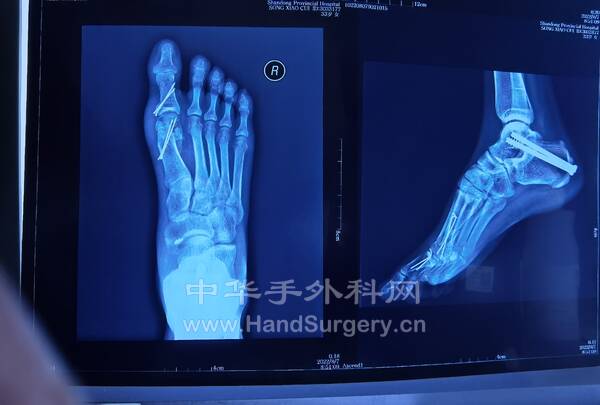

2.右跟骨闭合骨折切开复位钛板内固定术:取足跟外侧改良L形切口,逐层切开显露,剥离骨膜,显露骨折端,见距下关节变形,恢复跟骨高度,宽度及距下关节面,术中拍片示贝氏角,关节面角至正常范围,放置跟骨钛板1枚及螺钉9枚,逐层闭合切口,放置引流条2枚。